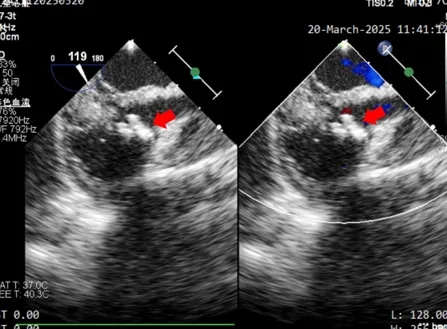

术中超声复测

膨出瘤基底部宽约7.6mm

两处破口分别宽约2.3mm及1.3mm